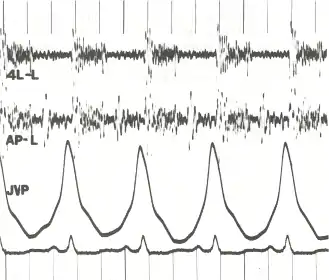

![]() Phonocardiogram and jugular venous pulse tracing from a middle-aged man with pulmonary hypertension (pulmonary artery pressure 70 mm Hg) caused by cardiomyopathy. The jugular venous pulse tracing demonstrates a prominent a wave without a c or v wave being observed. The phonocardiograms (fourth left interspace and cardiac apex) show a murmur of tricuspid insufficiency and ventricular and atrial gallops.[1] | |